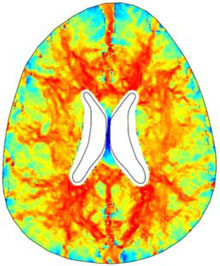

A numerical finite element model of one human brain is built in COMSOL in order to study a particular form of hydrocephalus, the so called Normal Pressure Hydrocephalus (NPH). The geometry of the ventricles and the skull is obtained by Magnetic Resonance Imaging (MRI) and imported in ... En savoir plus